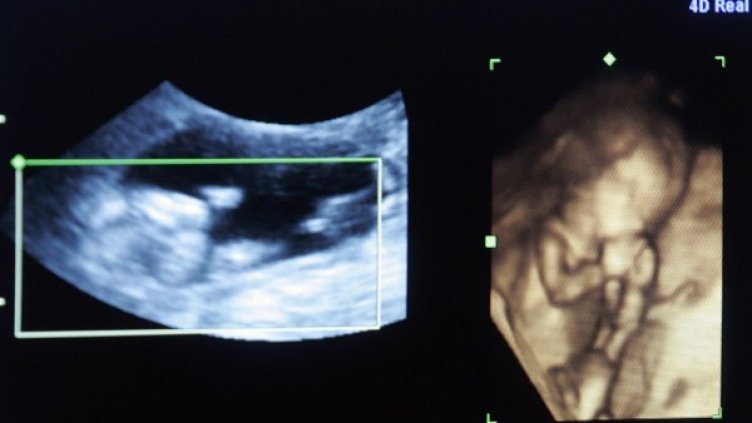

Трансфузията се извършва под постоянен ултразвуков контрол. Със специална игла се пробожда пъпната връв и бавно се инжектира подготвената кръв, като постоянно се следи състоянието на плода.